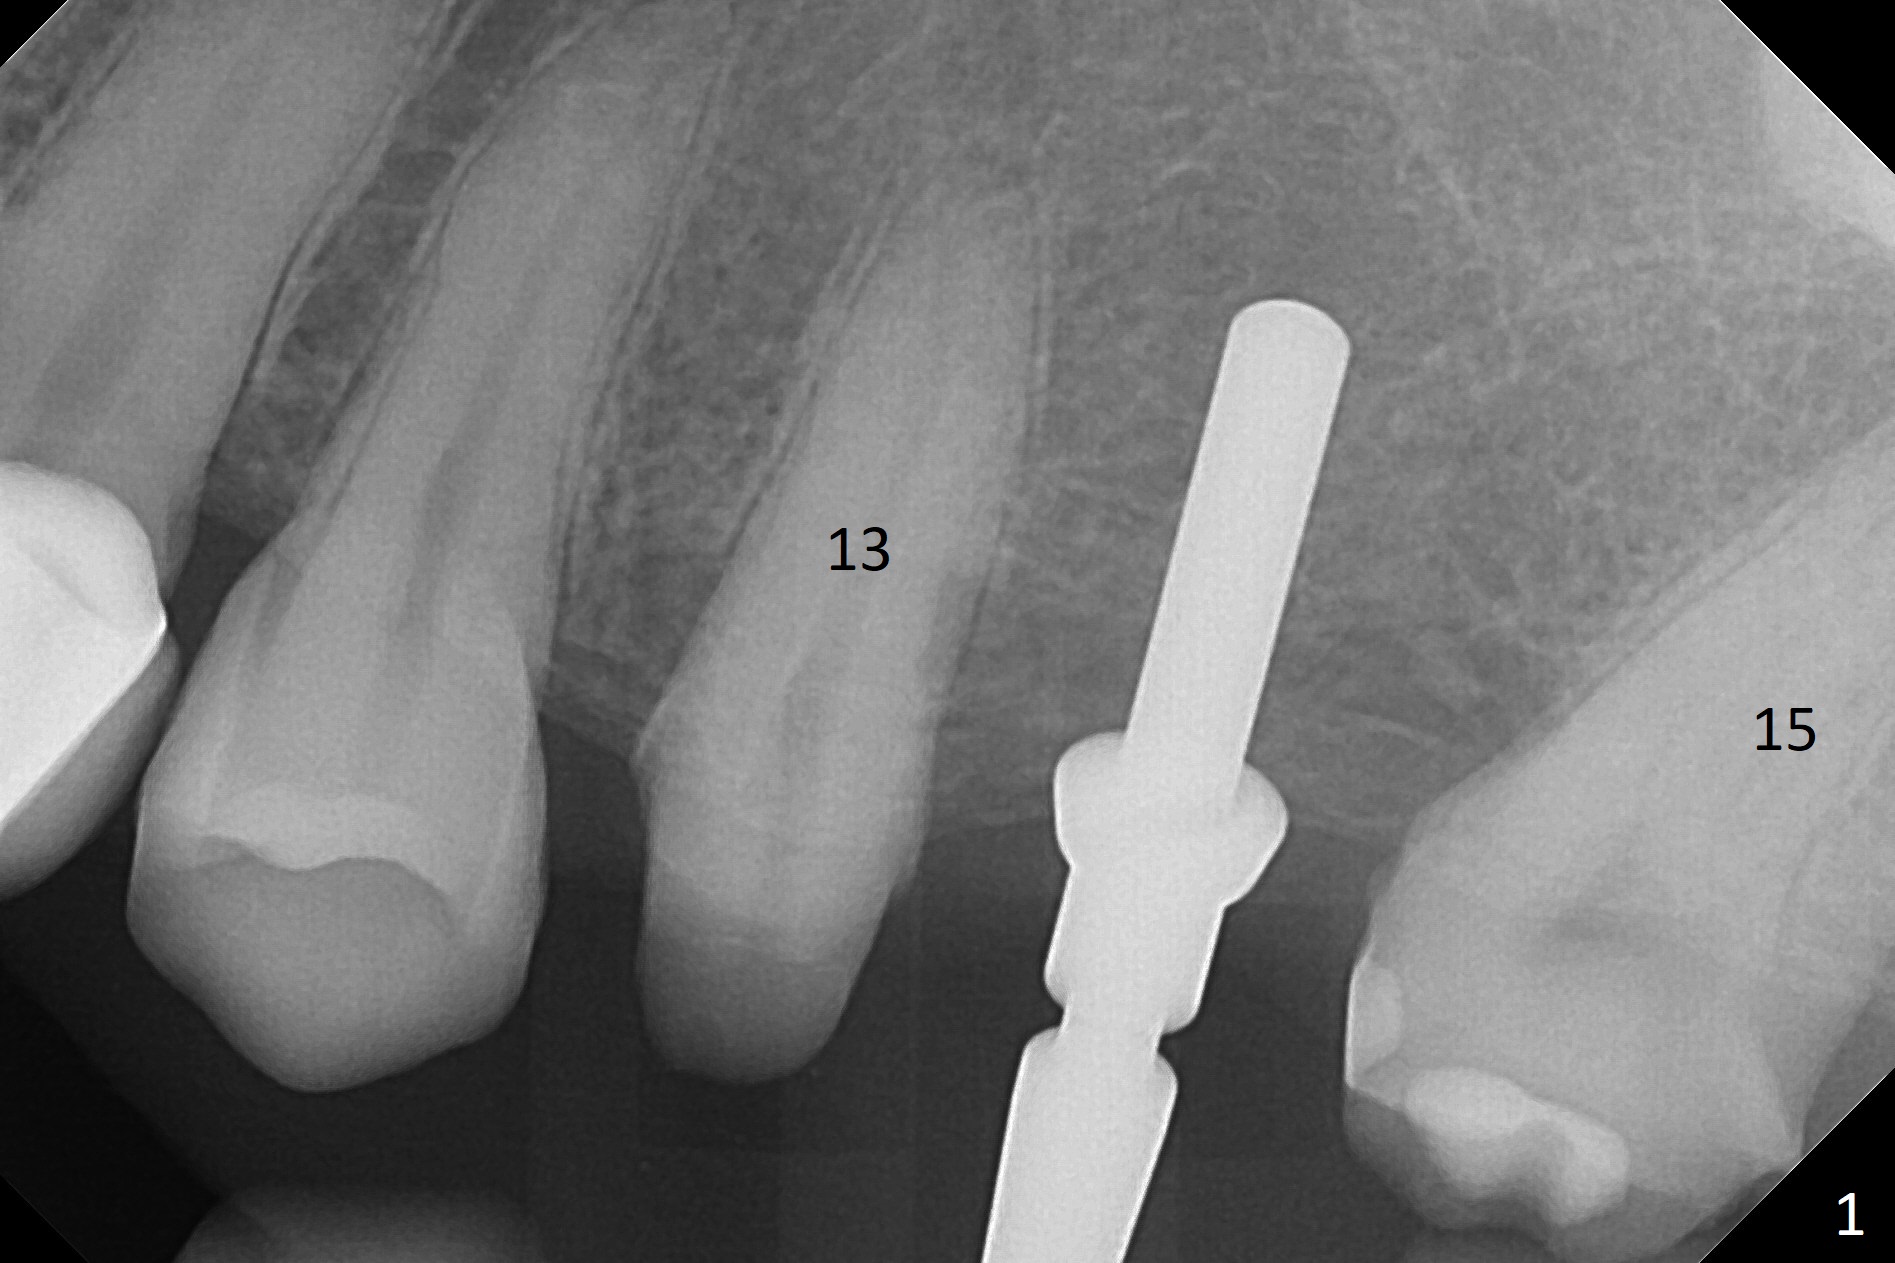

#13-15 FPD has not been used properly because of discomfort for 2 years. Before its removal, the discomfort derives from probing of the distal of #13 and mesial of #15, corresponding to calculus in the proximal areas. SRP is performed in UL quadrant after FPD removal. Bone density at the crest of the edentulous area is normal, while that of the medulla is low. After determination of trajectory and depth of initial osteotomy (Fig.1 (5 mm straight incision)), the site is underprep for a 4.5x13 mm Implant. Following adjustment, the implant is placed slightly subcrestal (Fig.2,3). It is possible that the discomfort of the previous FPD is due to overload, as suggested by the prominent buccal plate at #13 and 15, as compared to that of #12 (Fig.4 (5.2x4.5(3) mm cementation abutment at #14). Postop follow up shows that the tooth #15 may need RCT. The implant seems to enter the sinus (Fig.5 (2.5 months postop)) and be ready for restoration 3.5 months postop (Fig.6).